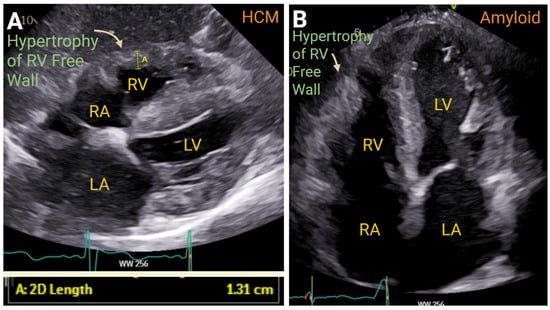

4.2. Right Ventricular Thickness

7.3. Cardiomyopathies